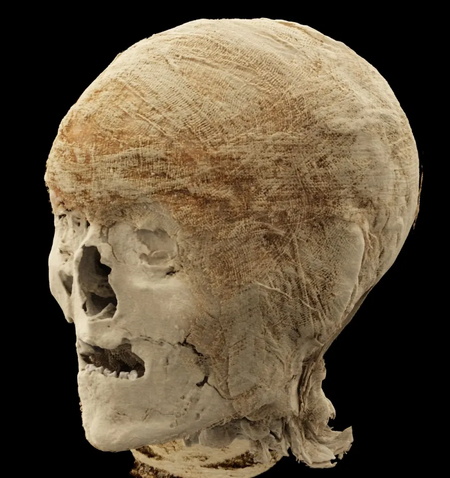

Công nghệ quét hình ảnh tiên tiến đã hé lộ mọi thứ, từ hộp sọ đến một bàn chân được bảo quản tốt với một phần lớn bị mất ở ngón chân cái.

Các chuyên gia đã xem xét hai hộp sọ với độ chi tiết đáng kinh ngạc.

Việc cố gắng nhìn xuyên qua các lớp bao bọc xác ướp mà không làm hư hại chúng là một thách thức lớn đối với các nhà khoa học.

Trước đây, các chuyên gia đã nhầm chiếc chân này với một con chim được ướp xác, nhưng công nghệ tiên tiến đã xác nhận chính xác tất cả các bộ phận trong đống đổ nát là gì - và chúng cũng cung cấp những chi tiết rùng rợn về hình dạng của chúng.

Họ ước tính rằng những di tích cổ nhất có niên đại từ năm 401 đến 259 trước Công nguyên, tức là chúng đã hơn 2.300 năm tuổi.

Mục đích chính của nghiên cứu là xem xét cấu trúc bên trong của các bộ phận cơ thể để tìm kiếm các dấu hiệu bất thường và hiểu rõ hơn về các kỹ thuật bảo quản bí ẩn mà người Ai Cập cổ đại đã sử dụng.

Nhìn chung, họ đã xem xét hai đầu, hai chi dưới bên trái, một bàn chân và một bàn tay.

Công nghệ quét hình ảnh tiên tiến đã hé lộ mọi thứ, từ hộp sọ đến một bàn chân được bảo quản tốt với một phần lớn bị mất ở ngón chân cái.

Các chuyên gia đã xem xét hai hộp sọ với độ chi tiết đáng kinh ngạc.

Công nghệ tiên tiến nhất đã được sử dụng để hé lộ thêm nhiều chi tiết về các xác ướp.

Việc cố gắng nhìn xuyên qua các lớp bao bọc xác ướp mà không làm hư hại chúng là một thách thức lớn đối với các nhà khoa học.

Trước đây, các chuyên gia đã nhầm chiếc chân này với một con chim được ướp xác, nhưng công nghệ tiên tiến đã xác nhận chính xác tất cả các bộ phận trong đống đổ nát là gì - và chúng cũng cung cấp những chi tiết rùng rợn về hình dạng của chúng.

Họ ước tính rằng những di tích cổ nhất có niên đại từ năm 401 đến 259 trước Công nguyên, tức là chúng đã hơn 2.300 năm tuổi.

Mục đích chính của nghiên cứu là xem xét cấu trúc bên trong của các bộ phận cơ thể để tìm kiếm các dấu hiệu bất thường và hiểu rõ hơn về các kỹ thuật bảo quản bí ẩn mà người Ai Cập cổ đại đã sử dụng.

Nhìn chung, họ đã xem xét hai đầu, hai chi dưới bên trái, một bàn chân và một bàn tay.